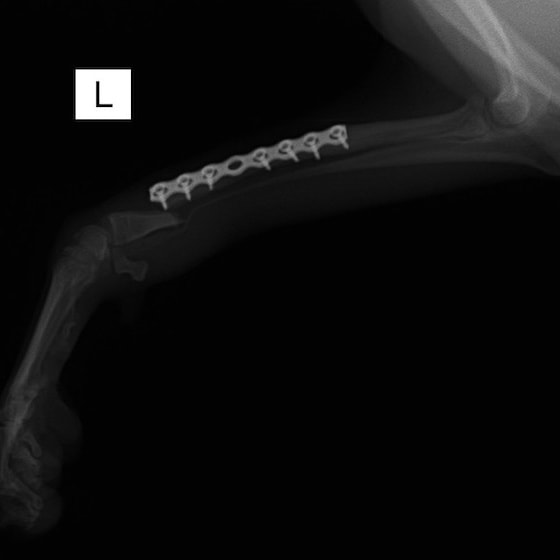

トイプードル 右遠位橈尺骨短斜骨折のALPSによる内固定

当院ではAdvanced Locking plate system(ALPS)と、Locking compression plate system(LCPS)という骨接合法で骨折症例の治療を行っています。

従来型のプレートのように広い面積で骨と接するプレートを用いて固定を行った場合、プレート下の骨はプレートとの接触面において血行が絶たれ壊死し、それがリモデリングされると骨密度が低下する。この骨密度の低下防ぐために、骨折部局所への血行を温存することの重要性が近年改めて認識されるようになってきている。Advaed Locking Plate System (ALPS)は従来型のプレートシステムの欠点を改良し、より使いやすく、より骨への血行を阻害しないようにというコンセプトで作られた。

Advanced Locking Plate System の特徴

- 骨への血行障害は最小限である

- 上下左右にベンディング可能でより3次元的な成形が可能

- すべての部位においてプレート強度は均一である

- ロッキングスクリューと圧着型スクリュー(皮質骨スクリュー)の双方が使用できる

- ダイナミックコンプレッション機能

- 生体親和性の高いチタン製

- トイ犬種から馬まで応用できるサイズ展開がある